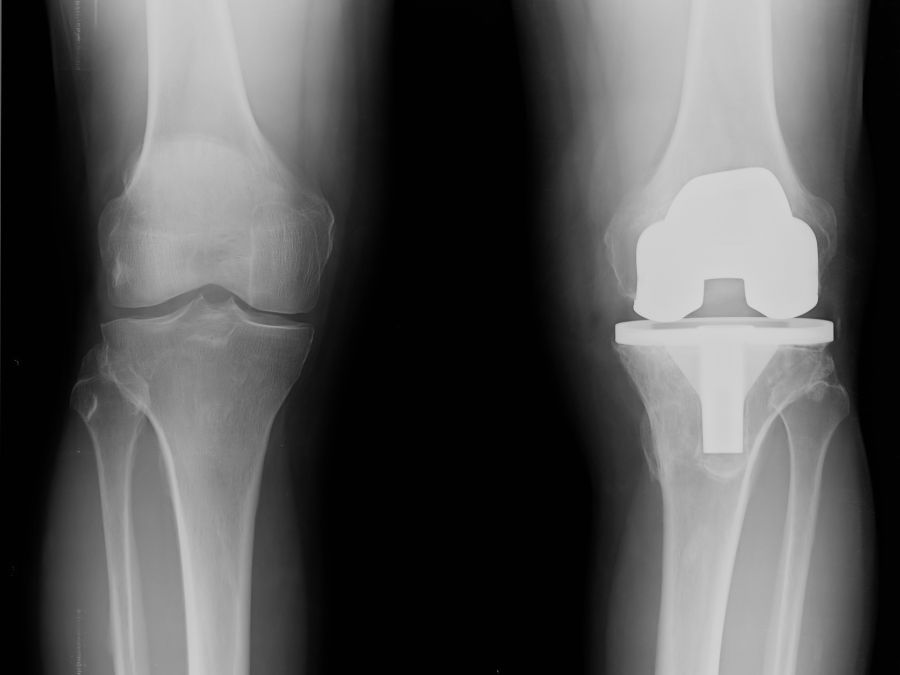

Per stabilire quale sia la tipologia di protesi più adatta al paziente è necessario conoscere con precisione lo stato dell’articolazione che andremo a sostituire. Se la malattia ha colpito tutta l’articolazione si utilizza la protesi totale, indicata quando i tessuti sono andati incontro a degenerazione in tutto il ginocchio e si procede con la sostituzione di tutti i comparti: mediale (interno), laterale e femoro-rotuleo. Si tratta di un approccio molto consolidato e sicuro che, proprio per questo motivo, un tempo veniva utilizzato anche quando l’artrosi colpiva un solo compartimento articolare. Si andava così a sostituire anche la parte del ginocchio ancora sana.

Oggigiorno ha preso sempre più piede l’utilizzo della protesi monocompartimentale, attraverso la quale si va a sostituire solo il compartimento articolare danneggiato, risparmiando i tessuti sani. Si tratta di un approccio meno invasivo che ha allargato la platea dei potenziali candidati all’impianto. Lo svantaggio di questo tipo di impianto risiede nella durata: nel caso l’usura dell’articolazione si dovesse allargare ai restanti compartimenti articolari, si renderà necessario un intervento di revisione – cioè nuovo intervento con l’impianto di protesi totale – in tempi relativamente brevi rispetto all’impianto della prima protesi.